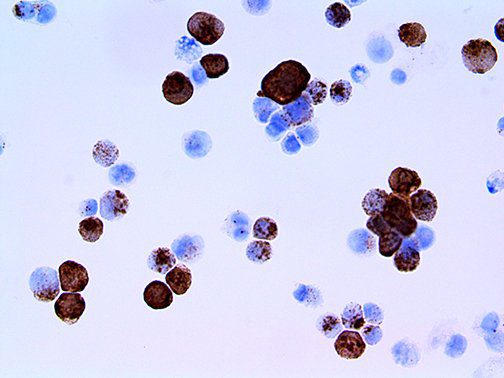

It is the ICU physician who is most likely to witness one of the deadliest manifestations of the abnormal immunological response, the cytokine storm syndrome (CSS). This response is also referred to by some as the cytokine release syndrome (CRS). CSS is characterized by continuous activation and expansion of macrophage and lymphocyte populations, which secrete large amounts of cytokines, causing the cytokine storm. This massive cytokine release is akin to hemophagocytic lymphohistiocytosis (HLH) disease, a syndrome characterized by initial unchecked and persistent activation of cytotoxic T lymphocytes and NK cells.

Clinical and laboratory manifestations of HLH include fever, enlarged liver and/or spleen, neurologic dysfunction, coagulopathy, liver dysfunction, cytopenias (i.e., low levels of erythrocytes, leukocytes, and/or platelets), hypertriglyceridemia, hyperferritinemia, hemophagocytosis, and eventually diminished NK cell activity as the immune system becomes progressively paralyzed. HLH can be familial (primary HLH) or secondary to another disease process (sHLH), such as rheumatic disease, in which it is referred to as macrophage activation syndrome (MAS, characterized by elevated ferritin).